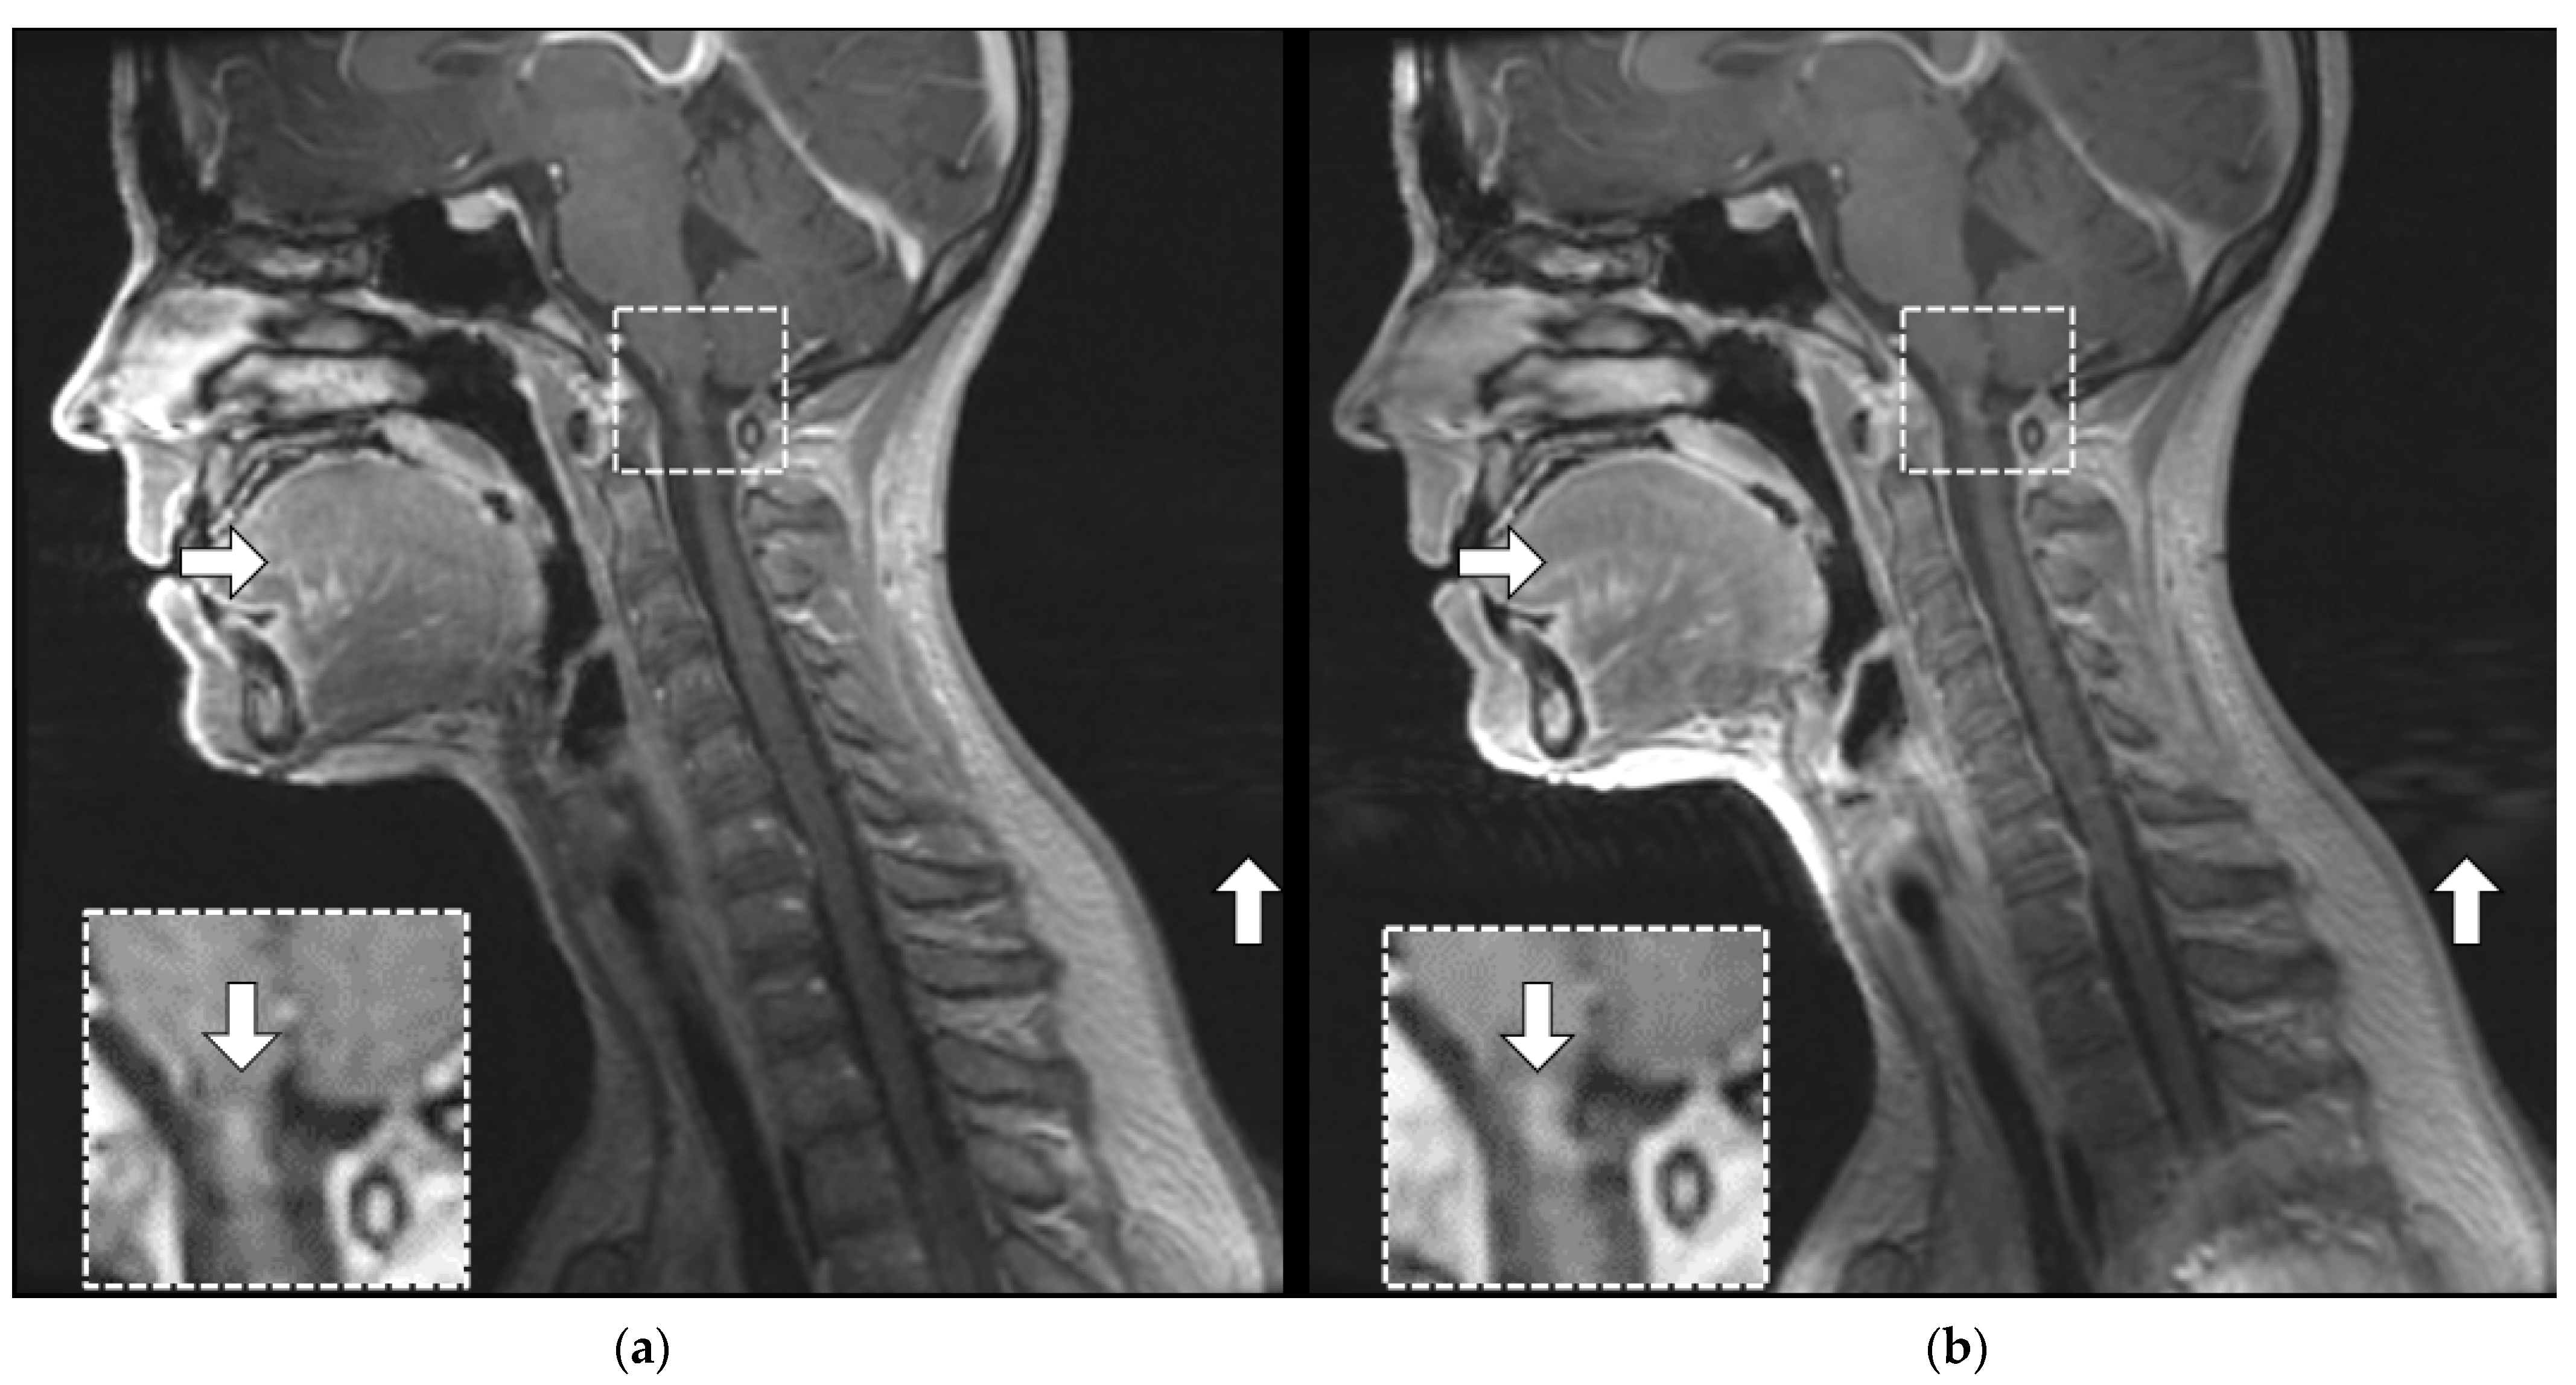

3.3.2. Artifact Enhancement